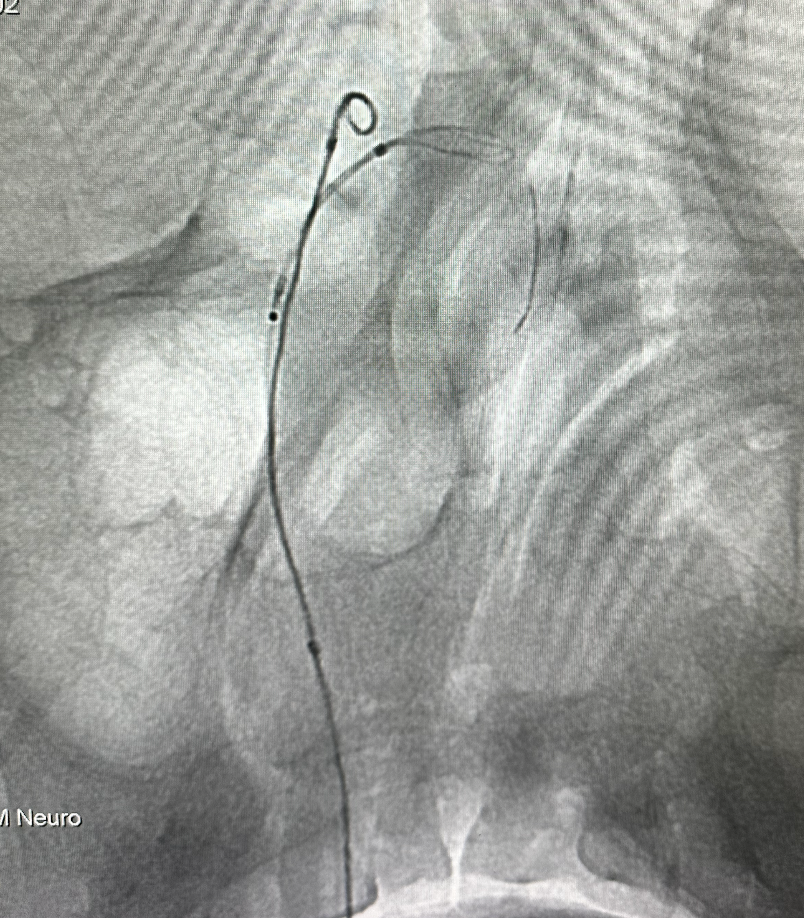

先将支架导管置入左侧大脑后动脉P2段,然后将直头微导管置入瘤体内,推出部分弹簧圈保护后半释放畅医达(TaminoVIA)颅内动脉瘤辅助栓塞支架